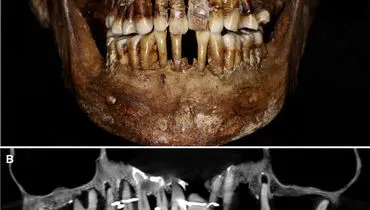

باستانشناسان بقایای یک «زن ریاضتکش» از دوره بیزانس را نزدیک بیتالمقدس کشف کردند که با زنجیر پیچیده شده بود و قدمت…